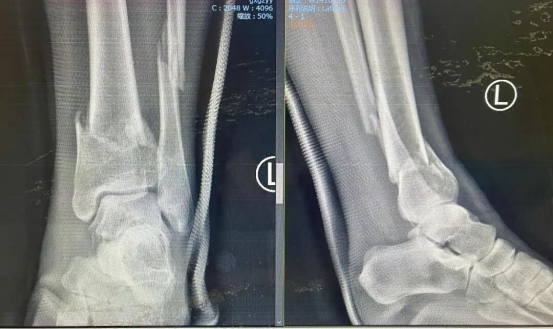

术前影像图

事发后,柯女士被送往北京一家医院,诊断为“左胫腓骨粉碎性骨折”,需手术治疗。但身处异乡,术后康复无人照料,让她倍感不便。与家人商议后,她决定返回柳州,选择在踝关节损伤治疗方面经验丰富的柳州市工人医院手足踝外科进一步诊治。

接诊后,刘毅团队迅速为柯女士进行三维CT检查,精准评估骨折移位与关节面损伤情况。考虑到患者年轻、对运动功能恢复要求高,团队制定了“微创复位内固定术”方案,采用MIPPO技术通过小切口植入钢板螺钉,最大程度保留关节活动功能。